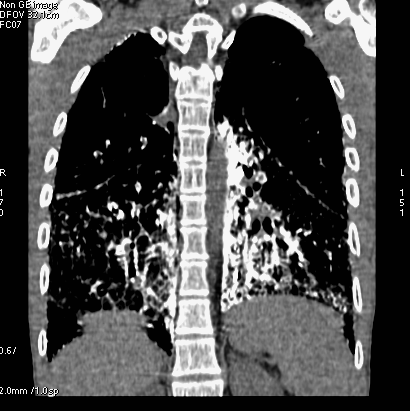

sesión 08-11 (tórax) jueves 24 de marzo a las 13,45

08-11-01 Sesión bibliográfica . Resumen del artículo :

Imaging of Incidental Findings on Thoracic Computed Tomography

Jeffrey B. Alpert MD and David P. Naidich MD Radiologic Clinics of North America Volume 49, Issue 2, March 2011, Pages 267-289. (CPG)08-11-02. Caso problema de radiología torácica

Varón de 30 años y origen norteafricano que consulta por disnea de cuatro meses de evolución.

Mujer de 65 años en estudio por disnea progresiva de años de evolución , actualmente es a mínimos esfuerzos.

Varón de 58 años que en enero de 2011 ingresa por cuadro de mialgias , astenia intensa , tos y fiebre de 5 días de evolución . Durante su ingreso presenta mal estado general e insuficiencia respiratoria que motiva su ingreso en UCI. Cultivos de esputo negativos. Antigenuria para neumococo y legionella negativos.